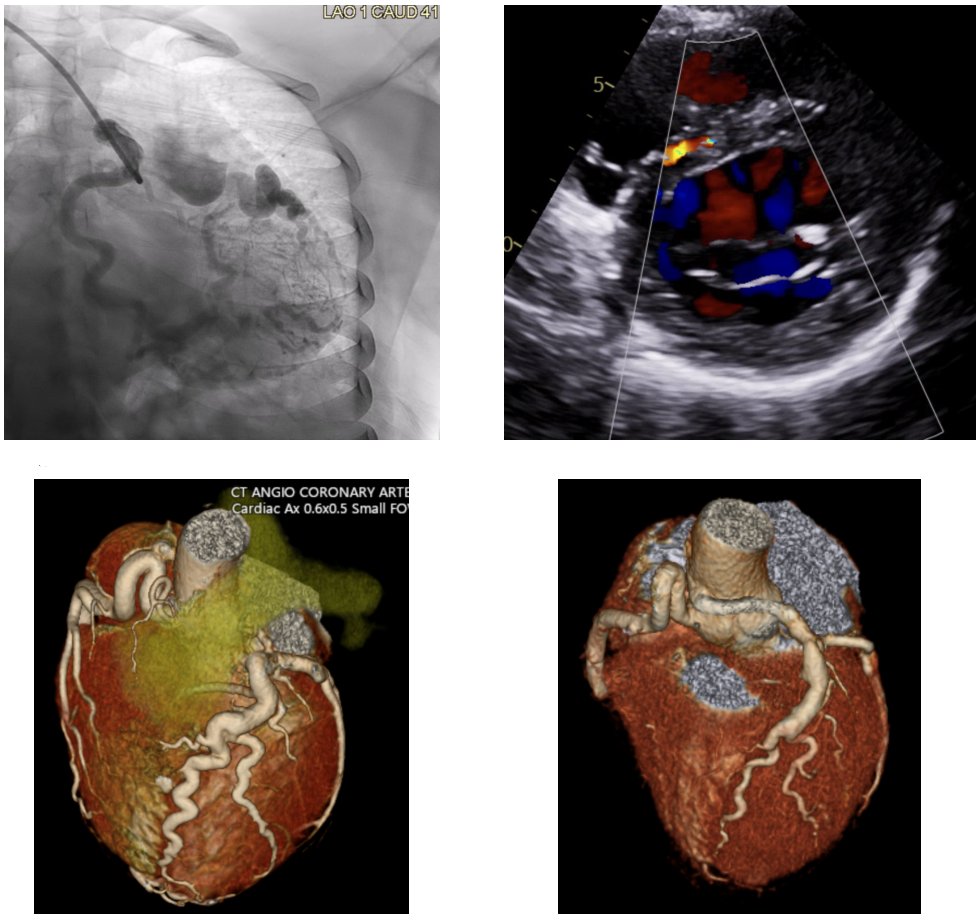

Our newest @JAHA_AHA review on the #RossProcedure is out today... a surgeon/cardiologist collaboration offering a modern look at patient selection, surgical technique, and long-term outcomes to guide practice.